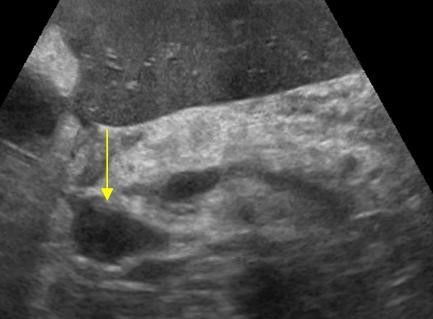

Мезентериальные лимфатические узлы: УЗИ и диагностика